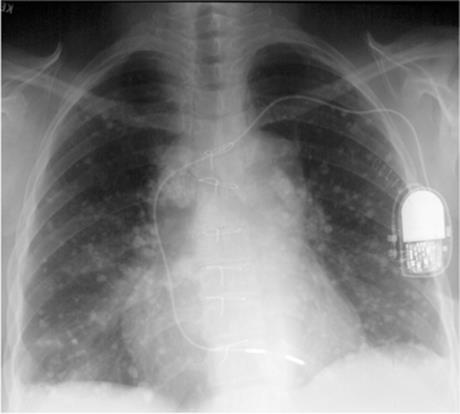

Figure 5.16 Pneumococcal pneumonia. (A) Posteroanterior and (B) lateral chest radiographs: homogeneous middle lobe pneumonia (P), possibly with slight expansion of the lobe, with associated right pleural effusion (E). (C) Later posteroanterior chest radiograph and (D)computed tomography: subsequent development of pneumatoceles (arrows) resulting in bronchopleural fistula with hydropneumothorax. P, pneumothorax; E, pleural effusion. Arrowheads mark gas–fluid level.

Initially, radiographs most commonly (75%) show multilobar homogeneous airspace disease (Fig. 5.17). Subsequent radiographic deterioration is often seen. Bilateral changes are noted in 35%. Cavitation or abscess formation (25%), pneumatoceles (40%), pleural effusions (33%), and pneumothorax (20%, often associated with pleural effusion or empyema) are other common findings. Pneumonia with pneumatocele or pneumothorax should suggest S. aureus as the cause.